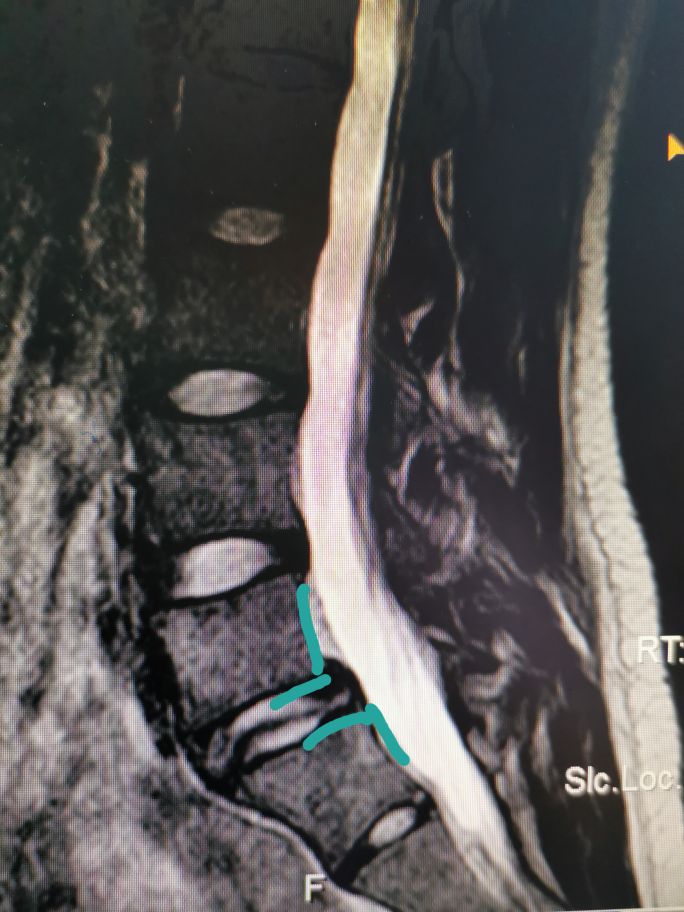

这样说比较抽象,其实最简单的办法就是把椎体分为四等份,超出1/4就是I度滑脱,超出2/4就是II度滑脱,依次类推。具体到这个病人,她上位椎体超出下位椎体1/4,那就是I度滑脱。那这个病人为什么会滑脱呢,也就是她属于何种类型的滑脱呢?首先她年纪很轻,不可能是退变性滑脱,大家看她的x线片:

圈子里面标记的部位是椎弓根峡部,大家看她的椎弓根那里已经断了,所以她这个属于椎弓根峡部裂导致的滑脱,也就是真性滑脱(椎弓根未断的滑脱是假性滑脱)。